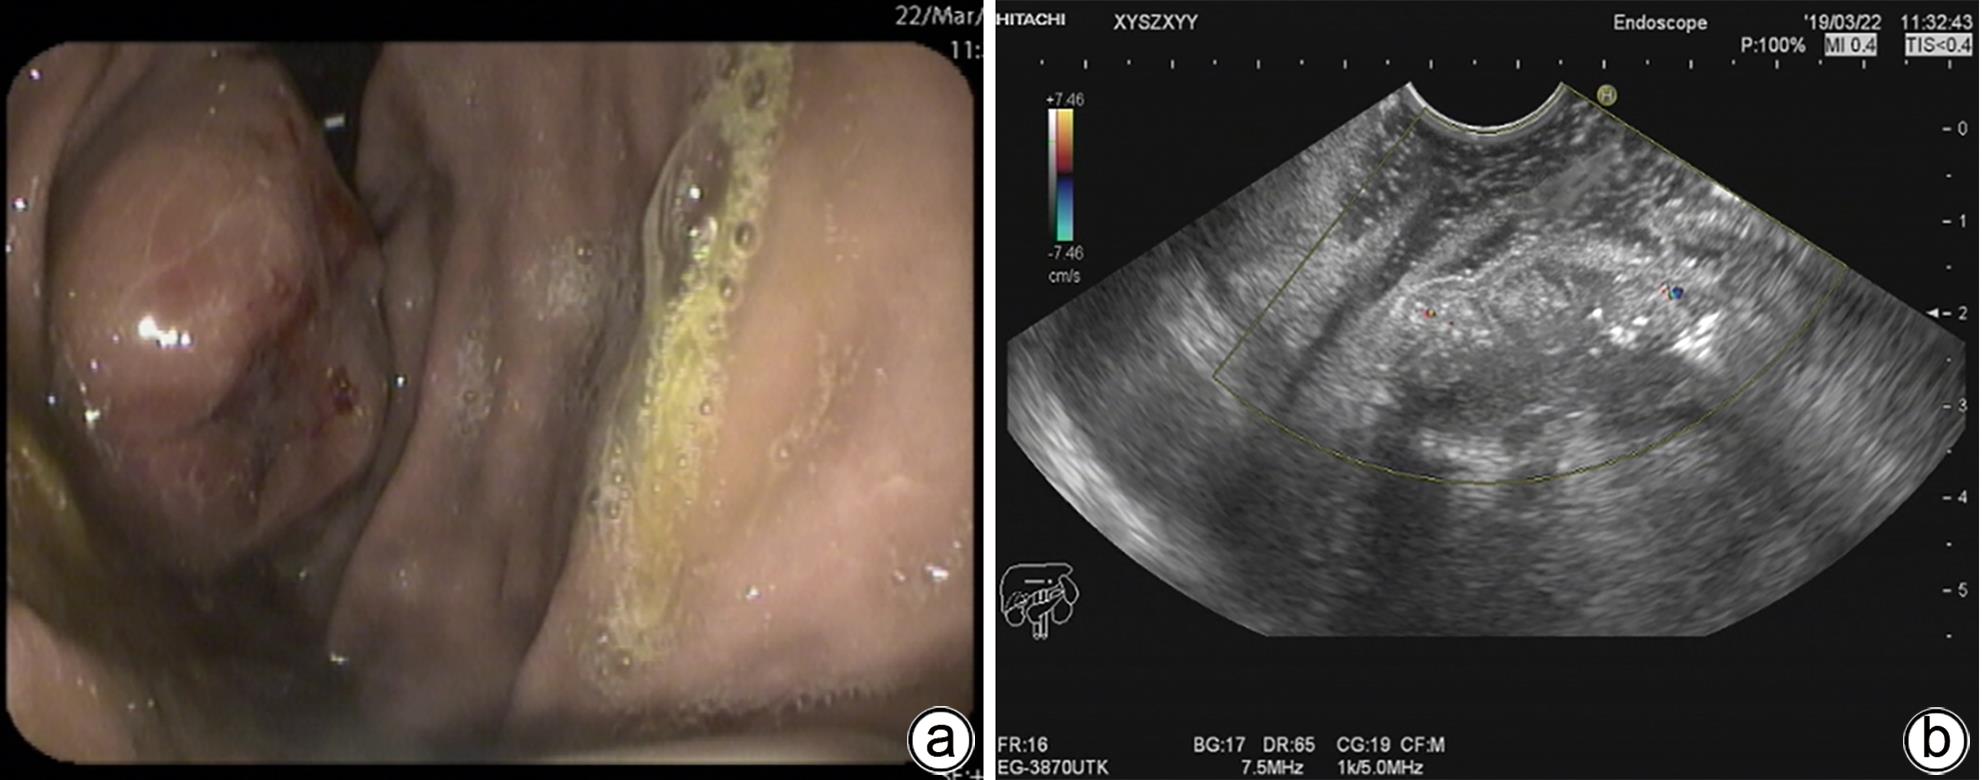

Efficacy of endoscopic ultrasound-guided coil placement combined with tissue adhesive injection in treatment of gastric varices with spontaneous shunt

Yafen TANG, Zhiyang JIANG, Dan LONG, Jinmin CHEN, Shan GAO

2024, 40(4): 739-744. DOI: 10.12449/JCH240416

Abstract(1096) HTML (592) PDF (917KB)(78)

Abstract:

Objective  To investigate the efficacy, safety, and cost-effectiveness of endoscopic ultrasound (EUS)-guided coil placement combined with tissue adhesive injection in the treatment of gastric varices with spontaneous shunt.  Methods  A retrospective analysis was performed for the patients with acute gastric variceal bleeding and spontaneous portosystemic shunt who were hospitalized and received balloon-occluded retrograde transvenous obliteration (BRTO) combined with endoscopic tissue adhesive injection or EUS-guided coil placement combined with tissue adhesive injection in Xiangyang Central Hospital from March 2019 to September 2022. The two surgical procedures were compared in terms of efficacy (technical success rate, 5-day rebleeding rate, 1-year rebleeding rate, and time to rebleeding), safety (the incidence rate of ectopic embolism, the amount of tissue adhesive used, and the amount of lauromacrogol used), and cost-effectiveness (hospital costs and length of hospital stay). The t-test was used for comparison of normally distributed continuous data between two groups, and the Mann-Whitney U test was used for comparison of non-normally distributed continuous data between two groups. The Kaplan-Meier method was used to estimate the rebleeding. The chi-square test was used for comparison of categorical data between two groups.  Results  A total of 25 patients received successful EUS-guided coil placement and tissue adhesive injection, with a technical success rate of 100%, a median amount of 2.5 mL tissue adhesive used, a median amount of 11.0 mL lauromacrogol used, a mean length of hospital stay of 14.88±3.21 days, a mean hospital cost of 32 660.00±4 602.07 yuan, and a 5-day rebleeding rate of 0%; among these patients, 2 were lost to follow-up, and 23 patients with complete follow-up data had an incidence rate of ectopic embolism of 0% and a median time to rebleeding of 689 days. A total of 14 patients underwent modified BRTO combined with endoscopic tissue adhesive injection, with a technical success rate of 100%; a median amount of 5.0 mL tissue adhesive used during surgery, which was significantly higher than that used in EUS (U=39.000, P<0.001); a median amount of 10.5 mL lauromacrogol used during surgery; a mean length of hospital stay of 15.38±4.94 days; a mean hospital cost of 57 583.47±18 955.40 yuan, which was significantly higher than that used in EUS (t=-6.310, P<0.001); a 5-day rebleeding rate of 0%. No patient was lost to follow-up, and all 14 patients had an incidence rate of ectopic embolism of 0% and a median time to rebleeding of 244.50 days, with no significant difference between the two groups (χ2=1.448, P=0.229).  Conclusion  EUS-guided coil placement combined with tissue adhesive injection is a relatively safe and effective technique for the treatment of gastric variceal bleeding and has a high technical success rate, a low incidence rate of serious adverse events, and similar efficacy to BRTO, with higher safety and cost-effectiveness.